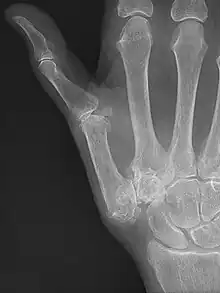

Osteoarthritis of the trapeziometacarpal joint

Diagnosis

TMC OA is diagnosed based on symptoms and signs.[8] Radiographs can confirm the diagnosis and the severity of TMC OA. Other diagnoses in this region include scaphotrapezial trapezoid arthritis and first dorsal compartment tendinopathy (De Quervain syndrome) although these are usually easy to distinguish.

TMC OA severity was classified by Eaton and Littler which can be simplified as follows:[21][22]

Stage 1:

• slight widening of the joint space

• < 1/3 subluxation of the joint (in any projection)

Stage 2:

• Osteophytes, < 2 mm in diameter, are present. (usually adjacent to the volar or dorsal facets of the trapezium)

Stage 3:

• Osteophytes, > 2 mm in diameter, are present (usually adjacent to the volar and dorsal facets of the trapezium)

• Slight joint space narrowing

Stage 4 trapeziometacarpal osteoarthritis, with major subluxation of the joint.

Stage 4:

• Narrow joint space

• Concomitant scaphotrapezial arthritis

A simpler classification is no arthritis, some arthritis, and severe arthritis.[23] This simpler classification system omits the potentially contradictory details of the Eaton/Littler classification and keeps scaphotrapezial arthrosis separate.